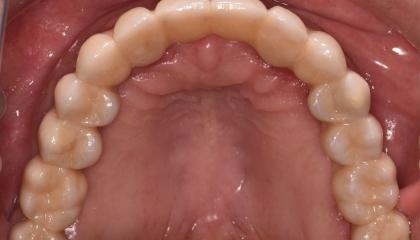

After